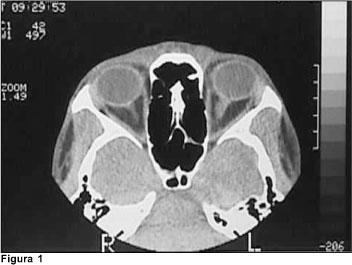

Dos exames de imagem, foram solicitados: tomografia de crânio, que evidenciou assimetria ventricular, às custas de diminuição de ventrículo lateral à direita e tomografia de órbita (Figura 1), que revelou ingurgitamento de veia oftálmica à esquerda. A ressonância de crânio demonstrou redução do fluxo em seio cavernoso à esquerda (Figura 2). A angiores-sonância de crânio demonstrou: redução acentuada do fluxo venoso através do seio transverso esquerdo, sigmóide, seio cavernoso e veia jugular homolateral, correspondendo a trombose nestes segmentos; veias tributárias de convergência apresentavam-se túrgidas e proeminentes (Figura 3).

O diagnóstico de trombose do seio cavernoso é eminentemente clínico e seu prognóstico é diretamente influenciado pelo tratamento precoce adequado(9). Após a suspeita clínica, solicitamos exames de imagem para confirmação diagnóstica, sendo o exame de escolha a ressonância nuclear magnética (RNM), seguida da angiorressonância de crânio(1).